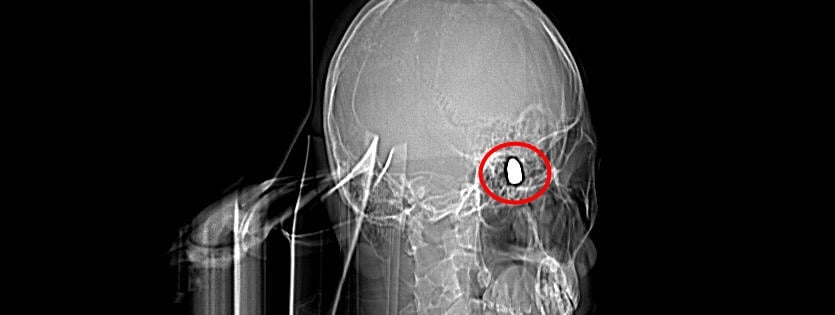

Çevredekilerin hastaneye götürdüğü Yusuf’un çekilen röntgeninde, başında mermi çekirdeği olduğu tespit edildi.

Doktorlar Yusuf’un başındaki merminin riskli bir bölgede olması sebebiyle çıkarılamayacağını söyledi. 4 gün yoğun bakım, 4 gün de serviste tedavi gören Yusuf düzenli olarak doktor kontrollerine gitti.